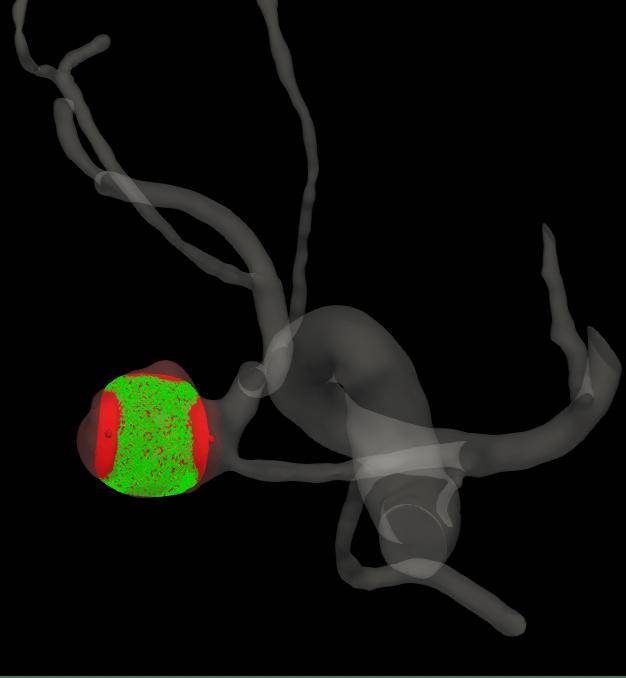

手术前,老张的脑血管造影数据被输入AI辅助系统,它迅速完成了脑部血管的三维高清重建,将错综复杂的血管结构清晰、立体地呈现出来。它不只展现图像,更进行了深度分析:AI技术自动分割动脉瘤最优瘤颈曲面,精准勾勒形态边界,并测量瘤体的大小以及与周围每一支血管的角度、距离。对于传统方式依赖个人经验的测量,AI系统提供了客观的数据支持。

图2:AI智能脑三维血管重建与自动分割